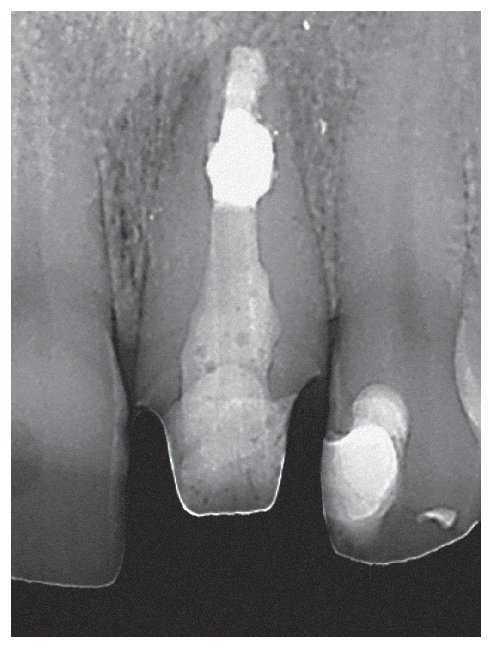

Figura 1a. Radiografía diagnóstica ortorradial del diente 43: una imagen radioopaca «interrumpe» el conducto radicular en el tercio medio de la raíz, fuerte curvatura apical del conducto radicular hacia mesial.

Figura 1b. En el segmento coronal de la raíz se observan dos conductos radiculares orientados en sentido vestibulolingual que están unidos por un istmo.

Figura 1c. En la proyección excéntrica de la conductometría se aprecia claramente la configuración tipo VI de Vertucci: los dos conductos radiculares están separados por un septo en el tercio medio y se unen nuevamente por debajo de éste mediante un istmo en el que se encuentran todavía restos de CaOH de la primera sesión. Los dos conductos muestran una trayectoria divergente en sentido apical para acabar en un foramen apical cada uno.

Figura 1d. Situación clínica en el momento de la adaptación del cono maestro para la compactación vertical en caliente.